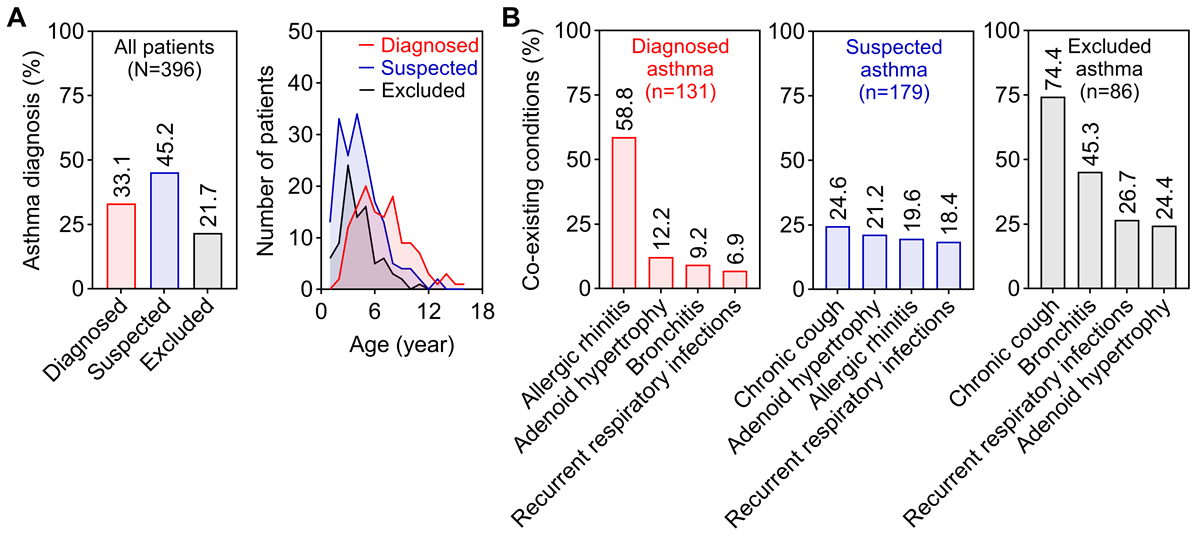

The CRCA successfully captured a predominantly young cohort, with 267 (267/396, 67.4%) children younger than 6 years. Patients were classified into 3 diagnostic categories: confirmed asthma (131/396, 33.1%), suspected asthma (179/396, 45.2%), and excluded asthma (86/396, 21.7%; A). Comorbidity profiles differed markedly among groups (B). Allergic rhinitis was most prevalent in the confirmed asthma group (77/131, 58.8%). Children in the excluded asthma group were most frequently diagnosed with chronic cough (64/86, 74.4%) or bronchitis (39/86, 45.3%). In contrast, the suspected asthma group showed a lower prevalence of additional diagnoses, suggesting a clinically distinct, “pure” early wheezing phenotype that is difficult to classify using current criteria.

As shown in , children with suspected or excluded asthma were significantly younger than those with confirmed asthma (P<.001), indicating that the under-6 age group largely comprises uncertain or excluded cases.

Three multivariable logistic regression models were constructed to identify factors associated with asthma diagnostic categories in this cross-sectional cohort (A). In Model 1 (suspected vs excluded asthma), respiratory infection as a wheezing trigger (odds ratio [OR] 4.41, 95% CI 2.16-9.42, P<.001), family history of allergic rhinitis (OR 2.27, 95% CI 1.08-4.99, P=.03), and higher blood eosinophil counts (per 100 cells/μL, OR 1.32, 95% CI 1.05-1.73, P=.02) were significantly associated with suspected asthma (B). In contrast, bronchitis was associated with reduced odds of suspected asthma (OR 0.30, 95% CI 0.14-0.65, P=.002).

Model 2 (confirmed vs suspected asthma) showed that confirmed asthma was associated with older age (per year, OR 1.29, 95% CI 1.14-1.47, P<.001), allergic rhinitis (OR 4.06, 95% CI 1.99-8.31, P<.001), and aeroallergen sensitization (OR 3.83, 95% CI 1.91-7.66, P<.001). Bronchitis remained negatively associated with confirmed asthma (OR 0.21, 95% CI 0.06-0.80, P=.02). These association patterns were consistent in Model 3 (confirmed vs excluded asthma). The robustness of these findings was confirmed through sensitivity analyses (), supporting the clinical validity of the diagnostic stratification and highlighting specific features that distinguish asthma from alternative diagnoses.